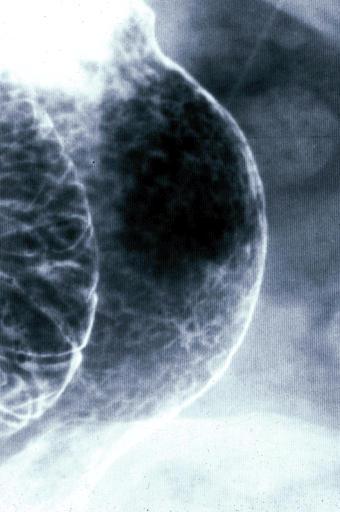

Minute type 0-IIc (superficial depressed type) early gastric cancer in the anterior wall near the greater curvature of the antrum.

Malignant epithelial tumor/Adenocarcinoma

Stomach/Angle

X-ray

Type 0/IIc (IIc) Superficial depressed type

1 - 9

mucosa